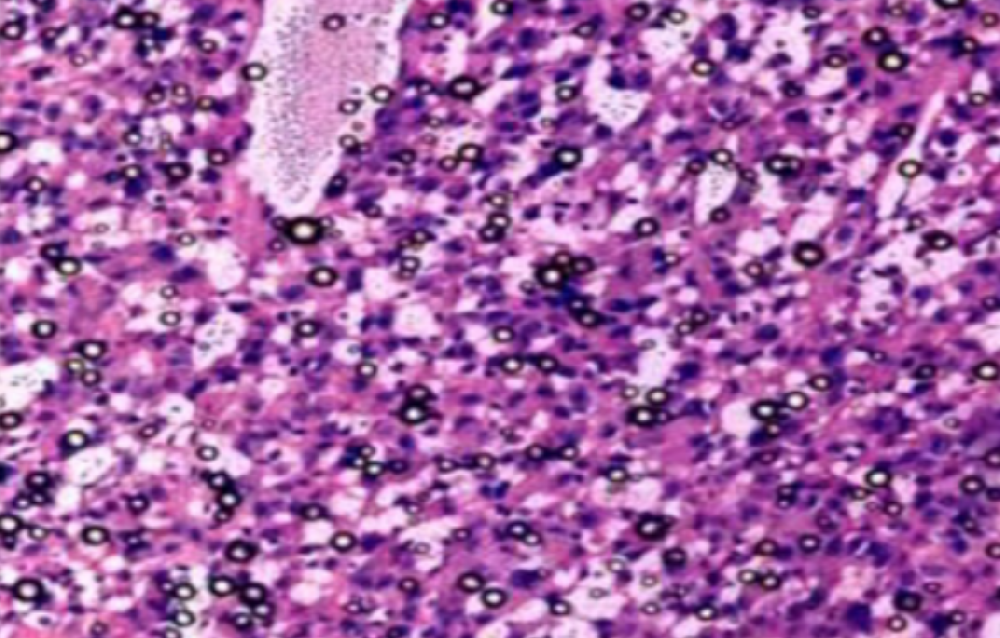

形成原因:切片经梯度乙醇处理后没有完全脱水,导致二甲苯透明、中性树胶封固后残留大量水分。 解决方法:首先移去盖玻片,用二甲苯溶解封固剂如中性树胶,再将切片置入无水乙醇内,待切片重新脱水完全后,用二甲苯透明处理,中性树胶封固。要注意所有用于脱水和透明的液体,在使用一定时间后,应及时更换。 二、细胞核呈红、棕色 形成原因:苏木精染色液过度氧化,切片在苏木精染液染色后返蓝不足。 解决方法:每次染色之前检查苏木精染色液的染色能力,发现苏木精染色液氧化过度应及时更换。此外,切片经苏木精染色后,要给切片以足够的蓝化时间,蓝化过程可用流水、温水、弱碱性溶液(如稀氨水或0.2%碳酸氢钠)等处理。 三、切片在脱蜡后出现大片白色斑点 形成原因:由于烤(烘)片温度太低,切片上的组织蜡膜在脱蜡前没有充分烤(烘)融化。或是因为切片在二甲苯液中停留时间不足,或二甲苯使用过久,造成的脱蜡不彻底。 解决方法:若是由于切片烤(烘)温度低所致,可以先用二甲苯去除切片上的封固胶,然后重新用二甲苯脱去切片上的石蜡,再进行后续染色。若是由于切片在脱蜡的二甲苯中停留时间不足或脱蜡二甲苯使用过久浓度不足所致,则需将切片退回到二甲苯中,停留较长时间,或更换二甲苯液体重新脱蜡,再入乙醇重新脱二甲苯,入0.5%盐酸水溶液褪色后,重新HE染色。 四、细胞核苍白暗淡,即苏木精染色太淡 形成原因:切片在苏木精染色液停留时间太短;苏木精染色液过度氧化,失去染色能力,不能再继续使用;分化步骤处理时间过长;固定不及时。此外值得注意的是,若骨组织细胞核暗淡,大多是脱钙过度造成的。 解决方法:切片重新染色。如果组织在酸性固定液(如Zenker、Bouin)或非中性缓冲甲醛液固定时间过长,细胞核染色能力将减弱,需增加其在苏木精染色液的时间,或用一些方法增加组织的嗜碱性,以改善细胞核的着色。例如,上述组织玻片可以使用Weigert铁苏木精染色液。如果组织是用Zenker液固定的,可将切片脱蜡后放在5%碳酸氢钠溶液3~4h,流水冲洗5min后染色。如果组织是用Bouin液固定的,可将切片脱蜡后放在5%碳酸锂1h,流水冲洗10min后染色。 五、细胞核过染,苏木精染液占据了细胞质 形成原因:玻片在苏木精染色液停留时间过长,或是切片太厚、分化步骤时间太短。 解决方法:如果不是因为切片太厚(用显微镜仔细上下微调,只有一二层细胞核层次),就需将切片进行脱色、漂白、重新染色,适当调整染色和分化时间。但如果确定是由于切片太厚导致的细胞核过染,则需要重新切片。 六、伊红着色淡 形成原因:可能是伊红染液pH值大于5,也可能是蓝化液残留过多,切片太薄,或是切片经伊红染色后在乙醇脱水时间过长。 解决方法:检查伊红染液pH值,必要的话,用乙酸将其调节在4.6~5.0之间,从而使伊红染色色彩艳丽。此外,确保每次蓝化步骤完成后,使用的弱碱性溶液被充分洗去,玻片上没有残留的弱碱性溶液。最后,检查切片的厚度,且脱水时不要让切片在低浓度乙醇中停留时间过长,因为含水多的低浓度乙醇会将切片伊红的颜色分化掉。 七、细胞质过染、分色不足 形成原因:伊红染色液浓度太高,特别是存在焰红燃料、四溴四氯荧光素钠。切片在伊红染色时间过长,或是切片在伊红染色后经乙醇脱水步骤时时间太短,而使乙醇分化伊红的作用不能产生,都能够使细胞质过染。 解决方法:适当稀释伊红染色液,减少伊红染色时间,或使切片在乙醇脱水等步骤时,停留时间相对均匀。同样,也要检查切片的厚度是否合适。 八、切片中出现蓝黑色沉淀物 形成原因:苏木精染色液中的金属膜黏附在玻片上。 解决方法:染色前仔细过滤苏木精染色液,建议使用半氧化苏木精染色液,如Gill苏木精染色液,可以避免过多的金属膜产生。 九、光镜下切片某些区域难以聚焦 形成原因:盖玻片上可能有封固切片的封固剂。 解决方法:移去盖玻片,重新用干净的盖玻片封片。检查切片封片方法,是人工手工封法,还是机器自动封法,如有问题及时调整。 十、封固剂从盖玻片与载玻片之间的缝隙回缩 形成原因:盖玻片弯曲或不平整,或是封固剂含二甲苯过多,稀释过度。 解决方法:移去盖玻片,重新找一张盖玻片,用干净的封固剂封片。如用手工封片法,保证在封固结束时,封固剂容器盖子为紧闭状态。且尽量使用小的容器盛装封固剂,一旦封固剂太黏稠,就可以选择废弃。 十一、细胞核呈灰蓝状态 形成原因:可能由于组织处理温度过高、过热,在液体石蜡中停留的时间过长。或是固定时间太短后,直接在高浓度的乙醇中进行了脱水处理。 解决方法:理论上来说,仅在组织浸蜡步骤才进行加热,组织不能在热蜡液中停留太久。如果由于某些原因不能进行下一步包埋处理,可将组织连同塑料包埋盒一并放置在室温空气中,冷却凝固,以备包埋。待需要包埋时再重新加温直至石蜡融化即可。组织在处理前必须确保固定良好,脱水最好能从低浓度的乙醇开始。 十二、类色素的点状结晶和黑色光滑细胞核 形成原因:这种裸核改变是因为切片封片前放置在空气中的时间太长,以至于二甲苯挥发,切片干燥。 解决方法:移去组织切片上的盖玻片和封固剂,重新处理。将切片水洗数分钟,然后重新脱水、透明、封固。封片过程中要保持组织切片的轻度湿润,尽量不要让其干燥。 十三、染色过淡或过浓 解决方法:如果染色过淡,可以增加染色剂的浓度、延长染色时间或更换新鲜的染色剂;如果染色过浓,则应减少染色剂的浓度或缩短染色时间。 十四、切片出现叠加褶皱 形成原因:新购买的玻片洁净度不够、用镊子撑开切片时操作不够熟练未能平整伸展,或玻片表面有油脂,切片粘贴不牢。另外,烤片时间不足、烤片温度过低或切片过厚造成切片脱落,都会造成重叠或有皱褶的情况。 解决方法:新购买的玻片最好能用硫酸清洁液浸泡一晚,然后流水冲洗干净。在适宜的温度下烤片时间宁长勿短,保证有充足的烤片时间和温度。另外,切片刀要锋利,才能切出厚薄适宜的切片,保证切片不会因为过厚而脱落。 十五、组织残缺不全或有刮划痕迹 形成原因:组织残缺不全是由于切片时修整蜡块时深度不够、组织没有全部暴露于切面。切片的刮划痕迹是由于切片刀的刀锋有缺口、包埋的组织有异物,或是钙化组织、骨组织及包埋石蜡有沙粒造成的。 解决方法:修整蜡块时保证组织块全部暴露于切面,切片时保证切片刀的锋利没刀口。同时在组织取材时去除手术异物和钙化组织。最后,骨组织要完全脱钙,这样可以保证切片的完整和平整美观。 *注:由于实验中导致结果出现误差的原因多种多样,以上内容仅供参考,具体根据实际情况进行判断。